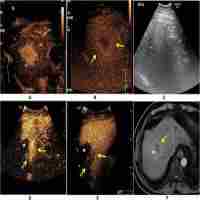

| Abstract | Aim. To explore acoustic radiation force impulse (ARFI) elastography in assessing residual tumors of hepatocellular carcinoma (HCC) after radiofrequency ablation (RFA). Materials and Methods. There were 83 HCC lesions among 72 patients. All patients were examined with ARFI, contrast enhanced ultrasound (CEUS), and CT or MRI. Tumor brightness on virtual touch tissue imaging (VTI) and shear wave velocity (SWV) were assessed before and approximately one month after RFA. Results. There were 14 residual tumors after RFA. VTI showed that all the tumors were darker after RFA. VTI was not able to distinguish the ablated lesions and the residual tumors. 13 residual tumor lesions were detected by CEUS. All completely ablated nodules had SWV demonstration of x.xx., while with those residual nodules, 6 tumors had x.xx measurement and 8 tumors had measurable SWV. nine lesions with residual tumors occurred in cirrhosis subjects and 5 lesions with residual tumors occurred in fibrosis subjects; there was no residual tumor in the normal liver subjects. Conclusion. VTI technique cannot demonstrate residual tumor post RFA. While SWV measurement of less than x.xx is likely associated with residual tumors, measurement of less than x.xx cannot exclude residual tumors. Liver cirrhosis is associated with decreased chance of a complete ablation. |